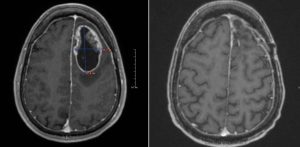

أفاد موقع “لايف رو” الروسي أن علماء من معهد علم الخلايا وعلم الوراثة، فرع سيبيريا التابع لأكاديمية العلوم الروسية، قاموا باختبار طريقة جديدة لعلاج ورم في الدماغ على الفئران عبر حقنها بفيروس زيكا.

ووفقا للمصدر ذاته ،فقد وجد العلماء ، خلال هذه التجربة ،أن الفيروس يهاجم الخلايا السرطانية ويبطئ نموها، من دون التسبب في ضرر كبير لبقية الجسم، حيث قاموا بحقن الخلايا السرطانية تحت الجلد، ويعتزم العلماء تكرار التجربة، حيث ستكون الخلايا السرطانية في الدماغ.

واضاف المصدر نفسه ،أنه في حال تأكيد النتائج، فإن هذا سيؤدي إلى إمكانية تطوير استراتيجية علاجية لعلاج أورام الدماغ لدى البشر. وأكد العلماء أن طريقة العلاج هذه لن تكون على مبدأ حقن المريض بفيروس زيكا بشكل كامل، وإنما تطوير عقار يعتمد على الفيروس ولا يشكل أي خطر على جسم الإنسان.